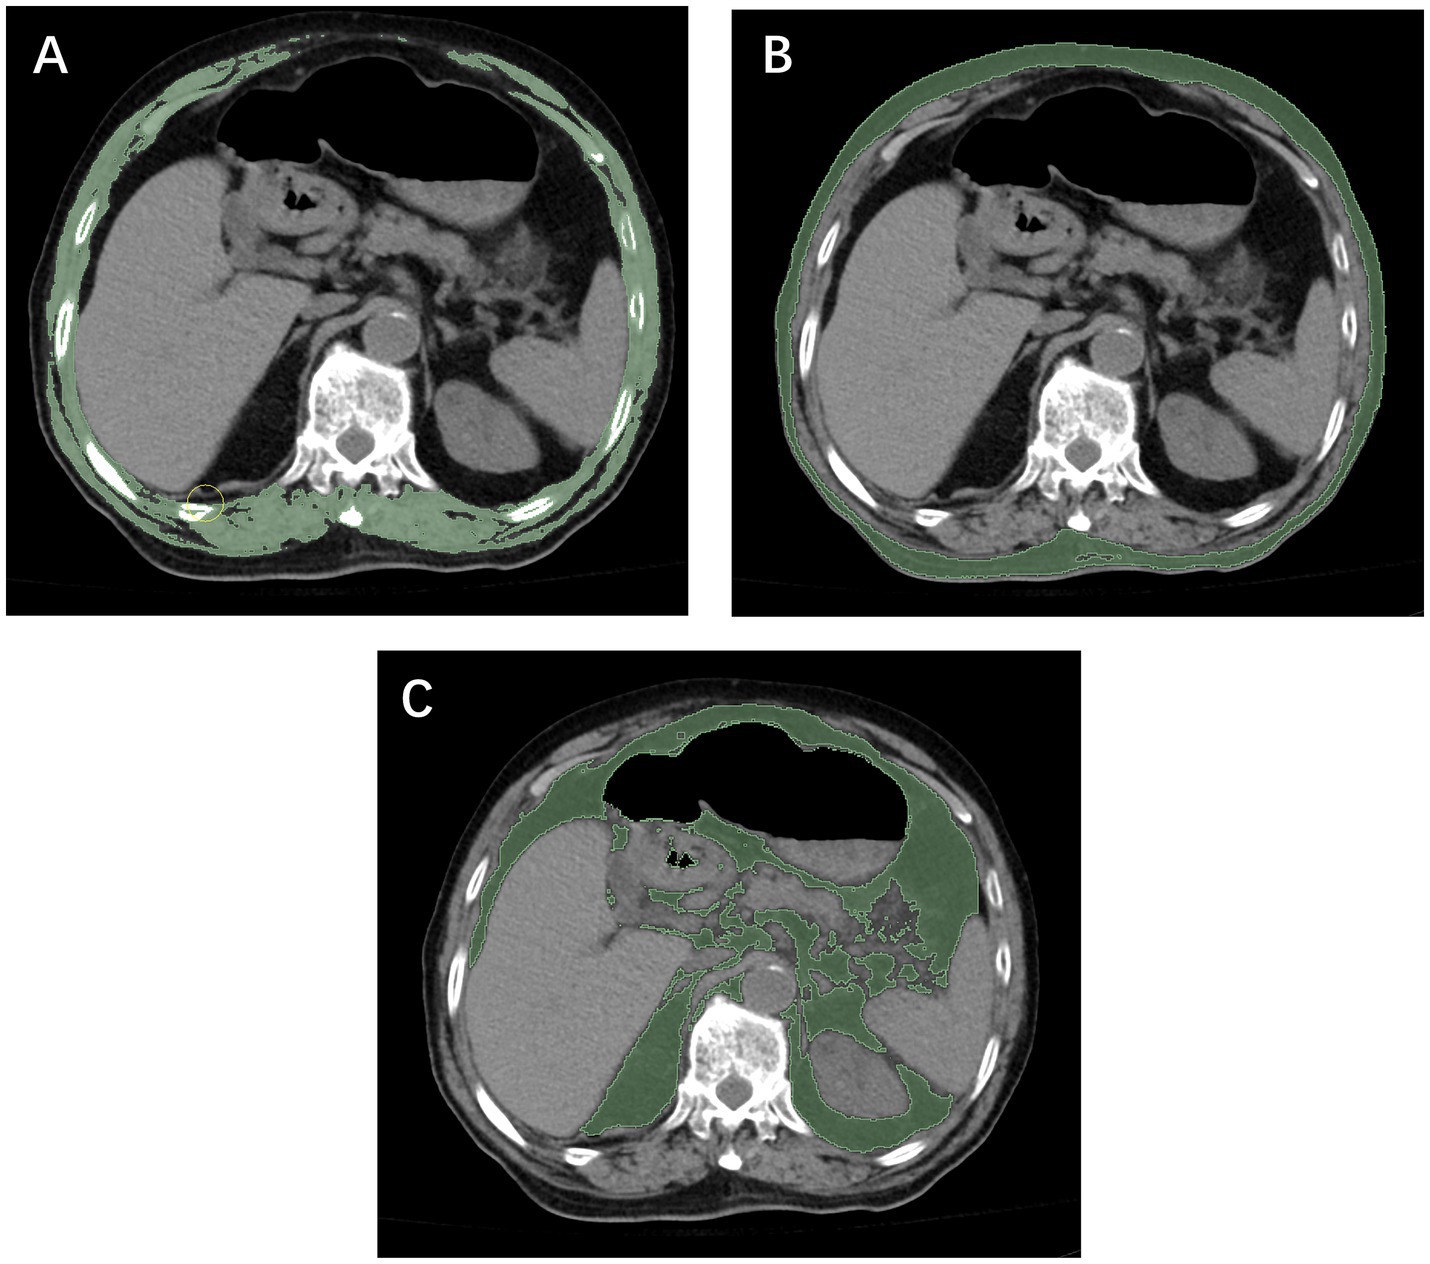

Figure 2. Measurement of the skeletal muscle index (A), subcutaneous fat index (B), and visceral fat index (C) using computed tomography at the T12 level.

Both institution 1 and institution 2 were affiliated with Wenzhou Medical University, and all diagnostic procedures and imaging protocols were conducted under the same standardized system. In both centers, unenhanced chest CT scans were performed using the same model of scanner (Philips Brilliance 16-slice, Philips Medical Systems, Eindhoven, the Netherlands), with identical acquisition parameters (120 kV, 250 mA, slice thickness 5 mm). All imaging data were stored in the institutional Picture Archiving and Communication System (PACS). Segmentation of skeletal muscle and adipose tissue was performed at the axial level corresponding to the mid-body level of the T12 vertebra using NIH ImageJ software (version 1.52c). Based on previously validated Hounsfield unit (HU) ranges (30, 31), skeletal muscle and adipose tissue were defined using ranges of −29 to 150 HU and −150 to −50 HU, respectively (Figure 3). The cross-sectional areas obtained were normalized to patient height by dividing by the square of the patient’s height (m2) to calculate the SMI, VFI, and SFI. Patients’ heights in this study were primarily obtained from hospital admission records, whereas for a small subset of patients unable to stand, measurements were taken at the bedside. Image analysis was performed by two radiological assessors, each with more than 5 years of clinical experience and proficiency in ImageJ. One assessor delineated the anatomical regions of interest, while the other independently reviewed the contours to ensure measurement accuracy.